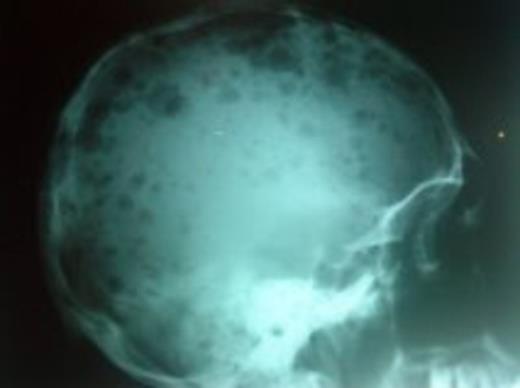

A 69 years old woman was sent at our institution for consultation due to pancitopenia at check-up. Past medical history was irrelevant. The CBC reported Hb 11.3 g/dL, Htc 33.8 %, ESR 32 mm/hr, Rouleaux formation +++, WBC 24.5 K/µL; differential showing nuetrophils 0.748 K/μL, lymphocytes 2.2 K/μL and myeloid blasts 20.1 K/µL, platelets 23.4 K/µL. The bone marrow aspiration was hypercellular with infiltration by myeloid blasts counting 95 %, and plasma cells with neoplastic morphology counting the remaining 5 %, no normal hematopoietic cells were observed. Hematological malignancy work up, also for MM, was performed, including flow cytometry (FC) and G band karyotype (GBK). FC revealed three populations: 1) representing 82.9 % that expressed CD11b +, CD13 ++, CD33 +, CD34 +, CD 38 +, HLA-DR + and MPO +; 2) representing 4.6 % and expressed CD38 +++, CD56 +, CD138 +++, kappa ++; 3) mixed population of normal B and T cells, representing 12.5 %. GBK showed 18 normal metaphases and 2 metaphases with t(11:14) (q13:q32) and del(13q). Stratification tests reported creatinin 2.3 mg/dL, , Ca 10.15 mg/dL, us-CRP 23 mg/dL, β-2-microglobulin 7.751 mg/L, albumin 2.35 g/dL, globulin 5.75 g/dL, serum protein electrophoresis with M-spike in the gamma region with 4.12 g/dL, positive Bence Jones protein, X-ray from the skull showed multiple lytic lesions. High risk MM and AML M4 were diagnosed. The patient did not accept any treatment and died few days later due a pulmonary hemorrhage.